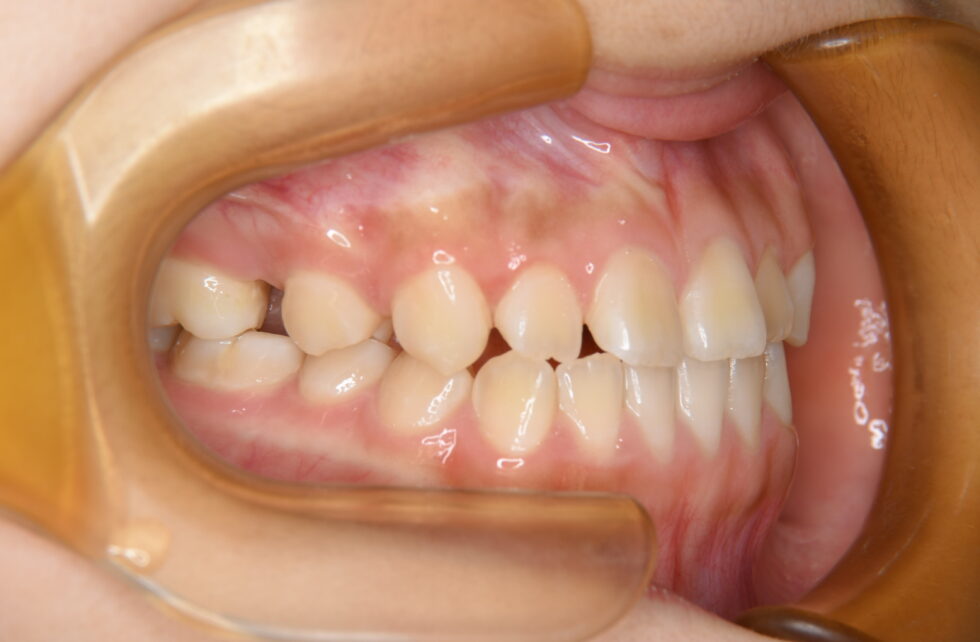

初診時年齢14歳の女子 上顎右側第二小臼歯の埋伏を主訴に遠方の歯科医院より紹介来院した。

埋伏している小臼歯は歯冠を遠心に向けて埋伏しており口蓋側面が歯肉から少し露出していた。また、歯列内に移動するための余地も5㎜程度不足しており、この余地を作ることと、埋伏歯の牽引を同時に行うことを目標に治療を開始した。近心を向いていた歯根の移動に時間を要し、頬舌側を逆転する形で歯列内に配列した。従って、頬側側にある口蓋側咬頭の咬合状態は甘いが、口蓋側にある頬側咬頭は咬合接触を得ることができた。動的治療3年3か月間で保定へ移行した。